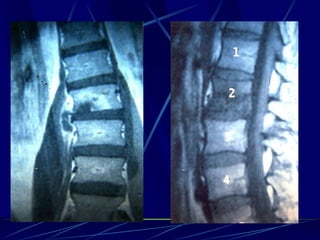

Epidural abscess

(Staphylococcus)